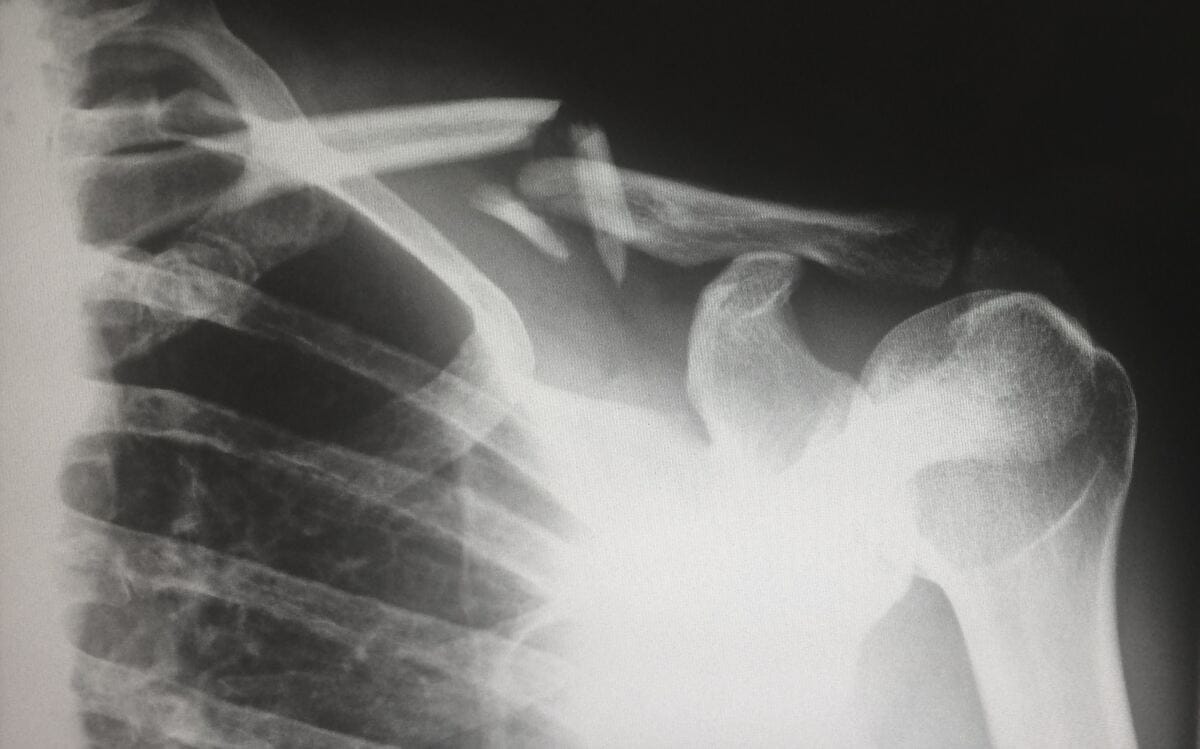

First, let's talk about bone density. Bone density refers to the amount of bone mineral and calcium that is present in your bones. The higher your bone density, the stronger your bones are and the less likely you are to experience fractures and other bone-related injuries. As we age, our bone density naturally decreases, which is why it's important to take steps to protect our bones.

Studies have shown that people who drink heavily are at a higher risk of developing osteoporosis, a condition in which the bones become weak and brittle. Osteoporosis is a serious condition that can increase the risk of fractures, particularly in the spine, hips, and wrists.